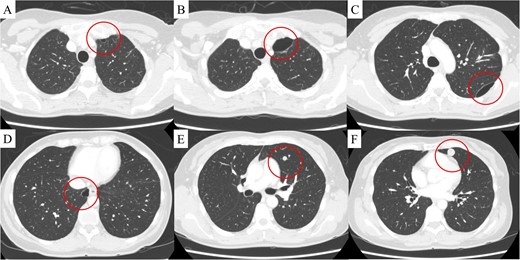

The patient was a 54-year-old woman with no history of smoking. Three years prior to being referred to our department, the patient had undergone total abdominal hysterectomy and bilateral salpingo-oophorectomy for a uterine STUMP. Six months thereafter, a single pulmonary nodule appeared in the left upper lobe (Fig. 1) and pulmonary metastasectomy was performed followed by four courses of gemcitabine-docetaxel therapy. One year thereafter, a single bulla was observed in the left lung (Fig. 2A). Subsequently, several bullae appeared and gradually developed (Fig. 2B–D); at referral, two additional pulmonary metastases were observed in the left lung (Fig. 2E and F). Because no other metastases were present, curative resection of the pulmonary metastases was planned. Additionally, we planned a bullectomy due to the lack of a reasonable explanation for bullae formation.

Computed tomography revealed a solitary pulmonary nodule (circle) in the left upper lobe 6 months after uterine surgery.

(A) Computed tomography revealed a bulla in the left upper lobe 1.5 years after uterine surgery. At 3 years, in addition to the development of the bulla in the left upper lobe (B), two more bullae appeared and gradually developed in the left (C) and right lower (D) lobes, and two pulmonary metastases appeared in the left lingular segment (E, F). The findings are indicated by circles.